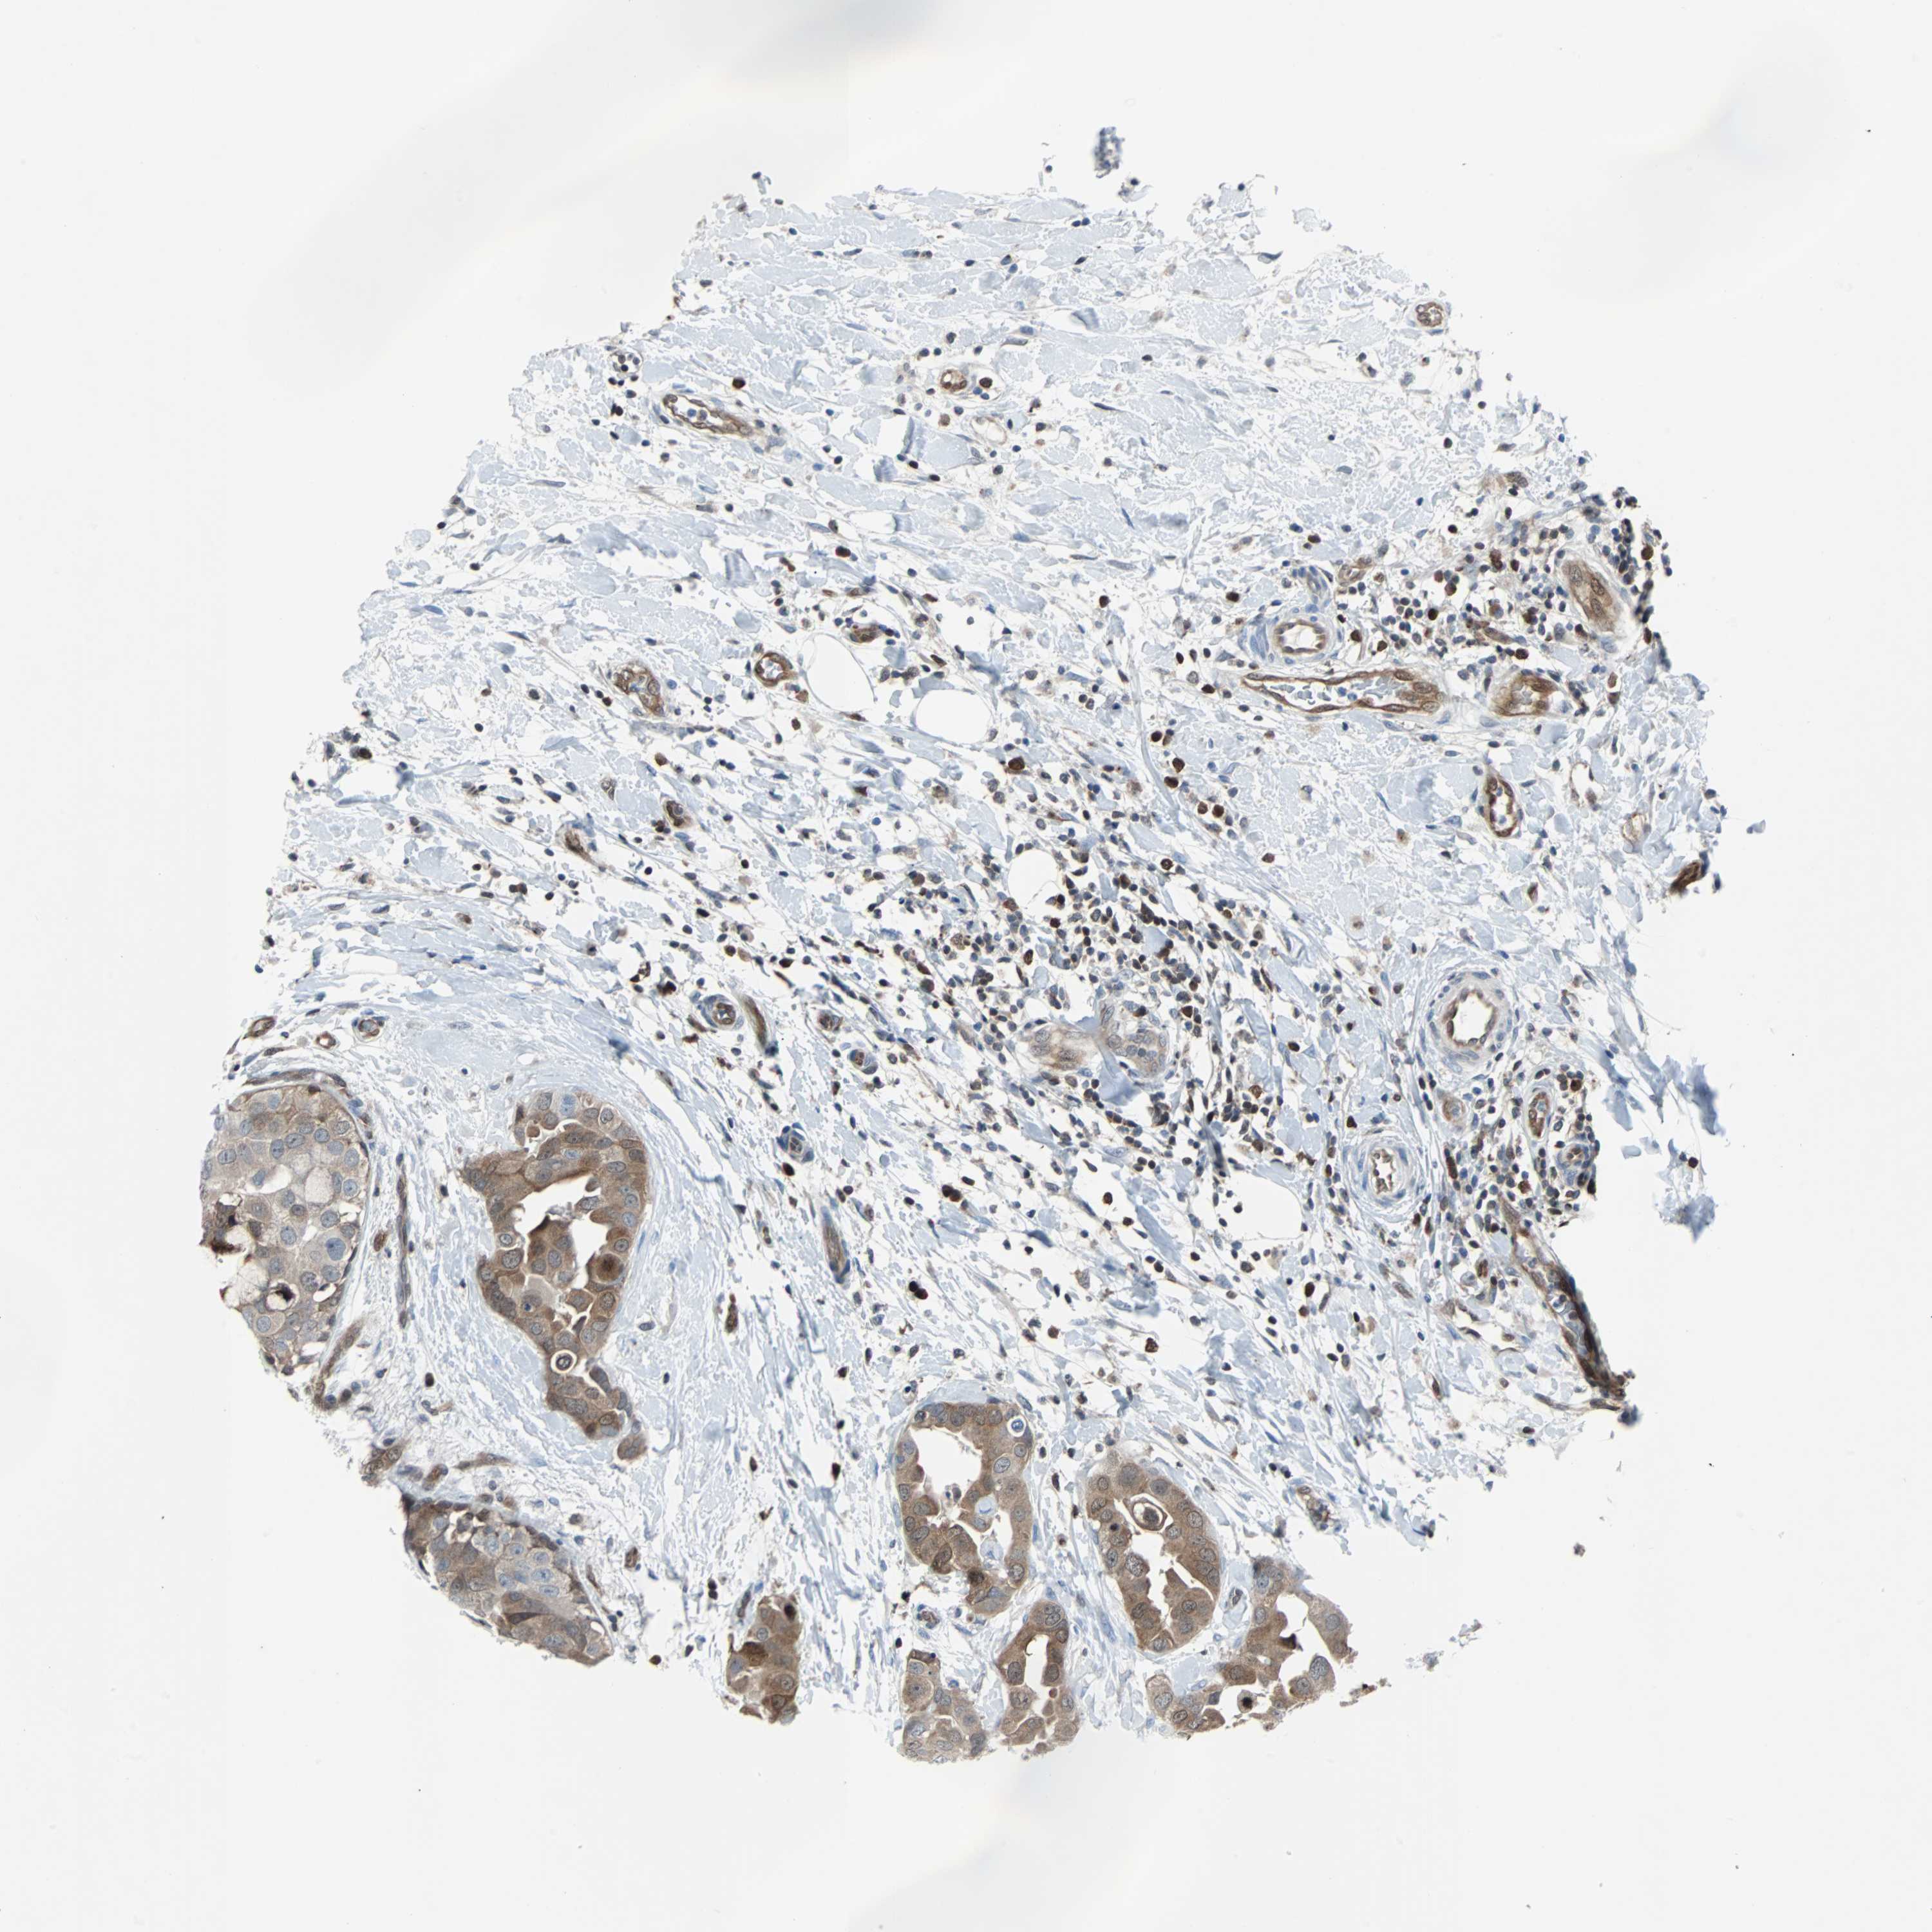

CANCER BREAST CANCER Show tissue menu

BRCA TCGA BRCA VALIDATION PROTEIN EXPRESSION